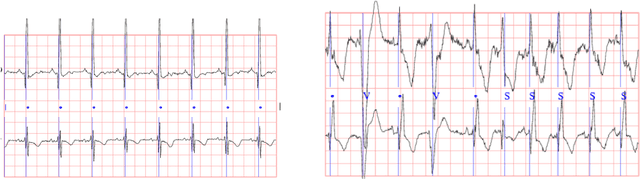

Abstract:Continuous medical time series data such as ECG is one of the most complex time series due to its dynamic and high dimensional characteristics. In addition, due to its sensitive nature, privacy concerns and legal restrictions, it is often even complex to use actual data for different medical research. As a result, generating continuous medical time series is a very critical research area. Several research works already showed that the ability of generative adversarial networks (GANs) in the case of continuous medical time series generation is promising. Most medical data generation works, such as ECG synthesis, are mainly driven by the GAN model and its variation. On the other hand, Some recent work on Neural Ordinary Differential Equation (Neural ODE) demonstrates its strength against informative missingness, high dimension as well as dynamic nature of continuous time series. Instead of considering continuous-time series as a discrete-time sequence, Neural ODE can train continuous time series in real-time continuously. In this work, we used Neural ODE based model to generate synthetic sine waves and synthetic ECG. We introduced a new technique to design the generative adversarial network with Neural ODE based Generator and Discriminator. We developed three new models to synthesise continuous medical data. Different evaluation metrics are then used to quantitatively assess the quality of generated synthetic data for real-world applications and data analysis. Another goal of this work is to combine the strength of GAN and Neural ODE to generate synthetic continuous medical time series data such as ECG. We also evaluated both the GAN model and the Neural ODE model to understand the comparative efficiency of models from the GAN and Neural ODE family in medical data synthesis.